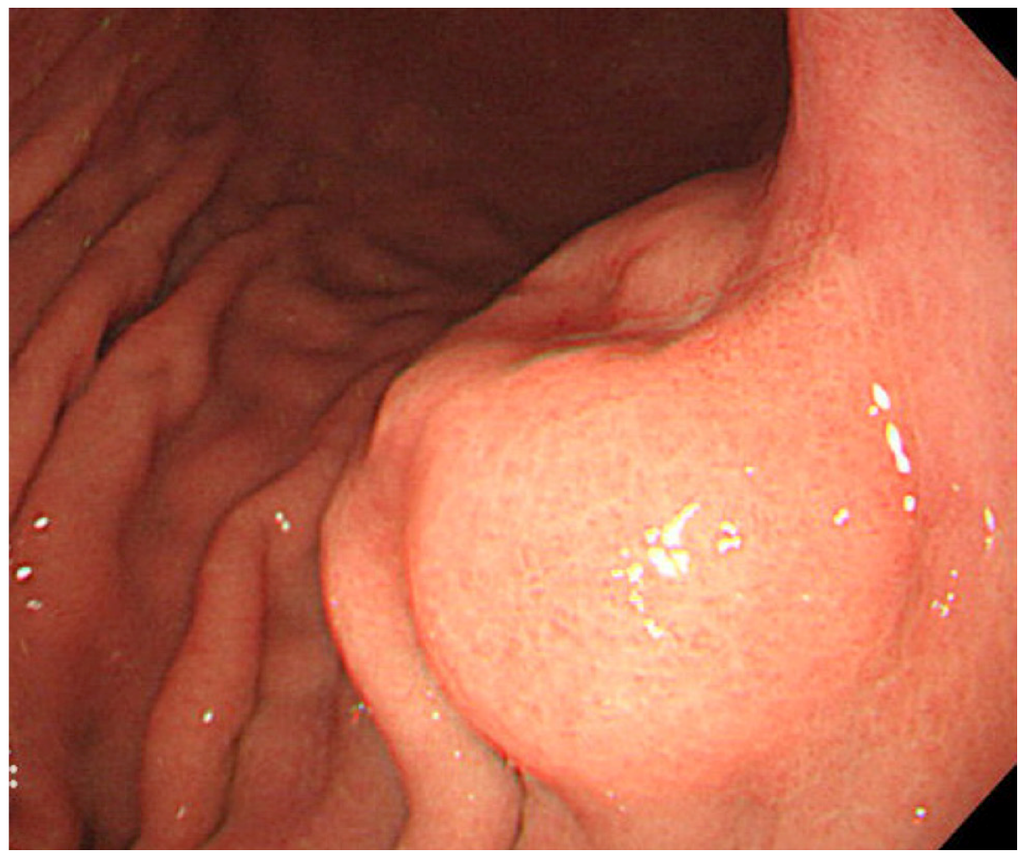

- Yanai, H.; Nishikawa, J.; Mizugaki, Y.; Shimizu, N.; Takada, K.; Matsusaki, K.; Toda, T.; Matsumoto, Y.; Tada, M.; Okita, K. Endoscopic and pathologic features of Epstein–Barr virus–associated gastric carcinoma. Gastrointest. Endosc. 1997, 45, 236–242. [Google Scholar] [CrossRef]

- Nishikawa, J.; Yanai, H.; Mizugaki, Y.; Takada, K.; Tada, M.; Okita, K. Hypoechoic submucosal nodules: a sign of Epstein–Barr virus–associated early gastric cancer. J. Gastroenterol. Hepatol. 1998, 13, 585–590. [Google Scholar] [CrossRef]